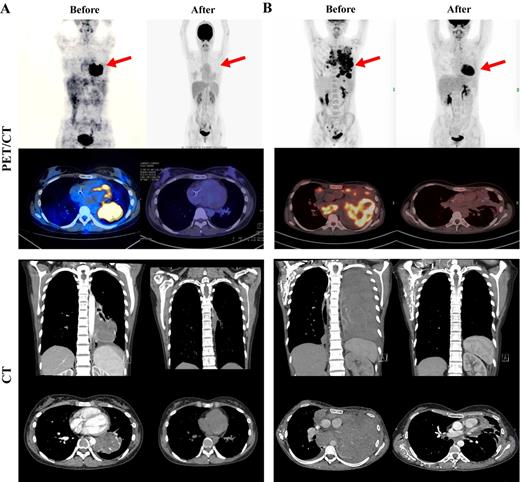

Results: Both HL patients relapsed after multi-line chemotherapies and radiotherapy. One patient relapsed after autologous hematopoietic stem cell transplantation. The main manifestations were cough and dyspnea caused by large lung masses. Both patients received 3 kinds of PD-1 blockade. One progressed after stopping Nivolumab and enrolled the clinical trial of decitabine and Camrelizumab for 6 courses and got stable disease(SD), then changed to Camrelizumab combined with ICE for 4 cycles and obtain complete metabolic remission(CMR). The other patient progressed with Nivolumab or Camrelizumab combined with A (B) VD regimen, and 2 courses of BV. She was then treated with Sintilimab combined with ICE for 4 cycles and obtain CMR. Both patients' cough and dyspnea were significantly improved, and lung lesions were significantly reduced after receiving 1 cycle of PD-1 blockade with ICE regimen and the quality of life was greatly improved. After 4 courses of treatment, the PET/CT assessment achieved CMR. The main side effect was a second-degree bone marrow suppression and can be tolerable for the patient.